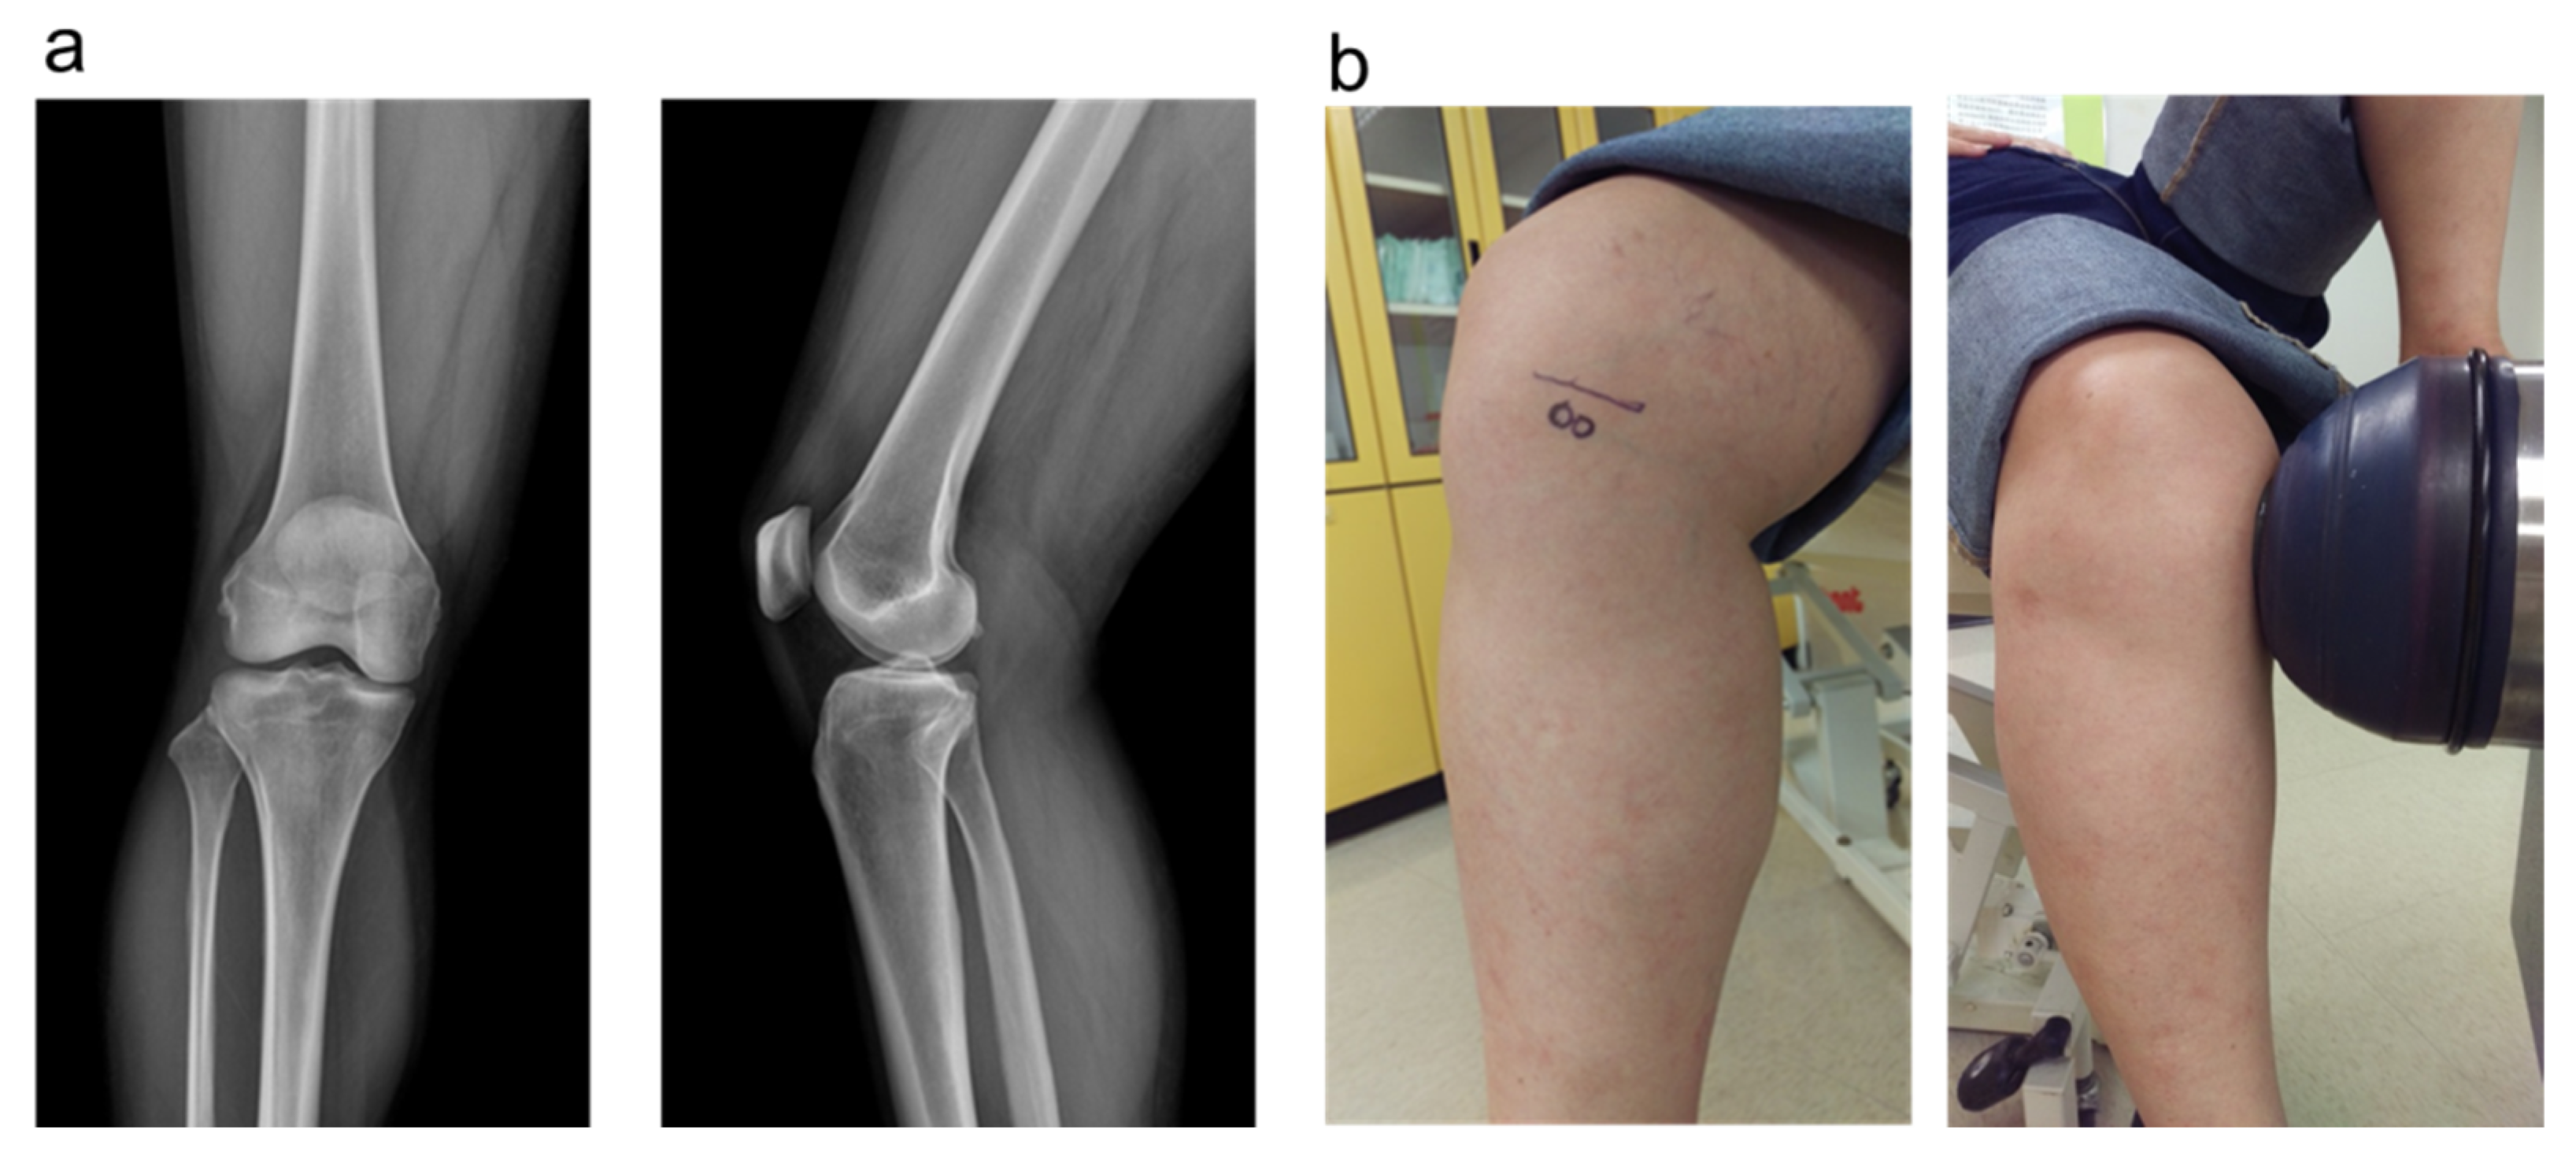

2.5. The Plain Radiographies and MRI